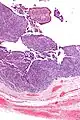

| Micrograph of transitional cell carcinoma of the ovary. H&E stain. |

TCC of the ovary is diagnosed by examination of the tissue by a pathologist. It has a characteristic appearance under the microscope and distinctive pattern of immunostaining.[2]